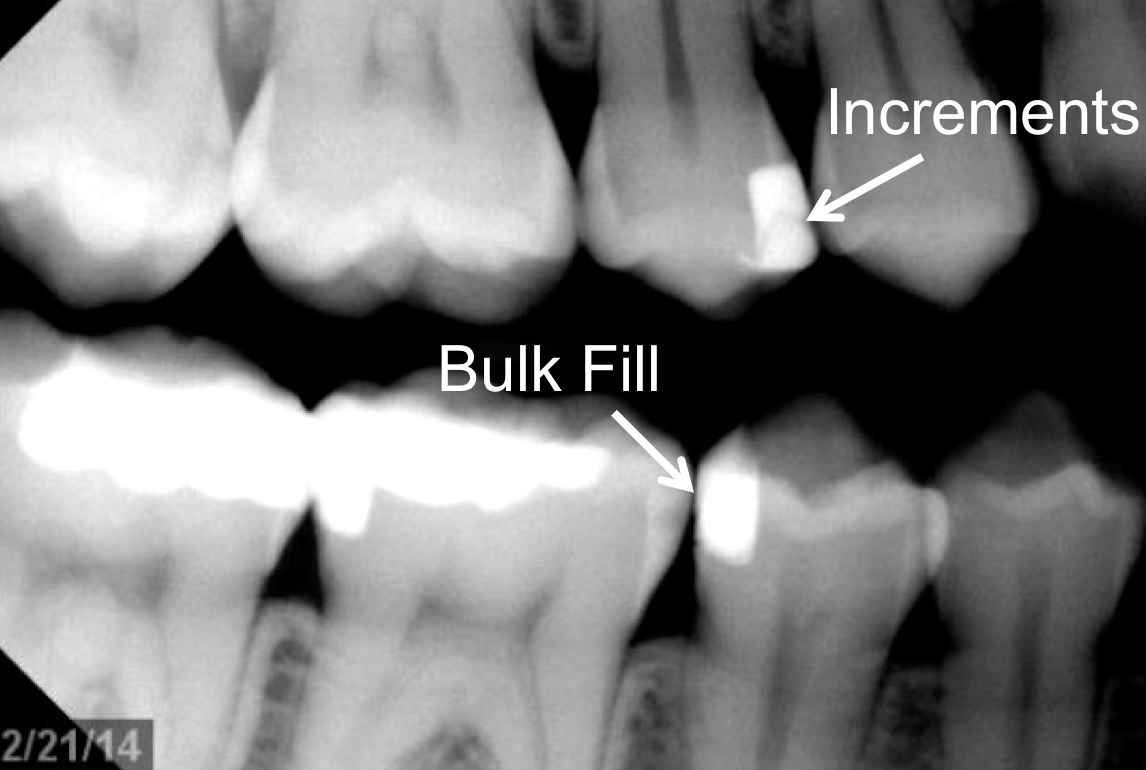

However, in the past decade, a new generation of low-shrinkage composites was developed specifically for bulk placement. These products’ advantages for placement relative to composites designed to be layered are radiographically apparent (Figure 1 and Figure 2); areas of porosity raise concerns about recurrent decay, and with a highly viscous composite, the chance of trapping air bubbles is significantly increased, compared to a dense, homogeneous void-free composite resin (Figure 2).2

Fig 2. Radiograph shows single 4-mm incremental bulk-fill placement compared to using a layered method.

Figure 2